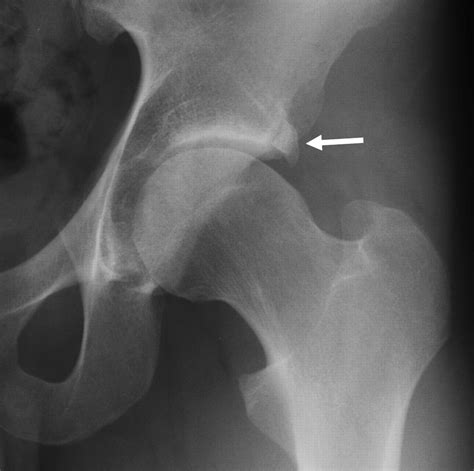

FAI is classified into three main types based on the shape of the femoral head and acetabulum:

• Cam Impingement: This occurs when the femoral head is not perfectly round, causing it to rub against the acetabulum during movement.

• Pincer Impingement: This happens when the acetabulum is too deep or covers too much of the femoral head, leading to excessive contact.

• Mixed Impingement: This is a combination of both cam and pincer impingement.